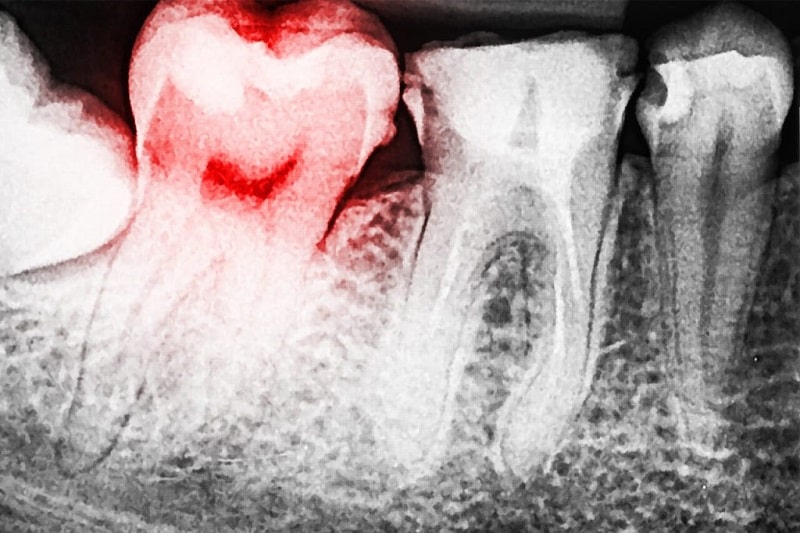

Đây là bước đầu tiên và là bước cơ bản trước khi thực hiện để nắm được tình trạng cơ bản liên quan đến cấu trúc răng của bệnh nhân. Sau đó, bệnh nhân sẽ được chụp X-quang răng để bác sĩ xác định chính xác vị trí, hướng mọc và tình trạng của răng từ đó đưa ra phương pháp nhổ răng phù hợp.